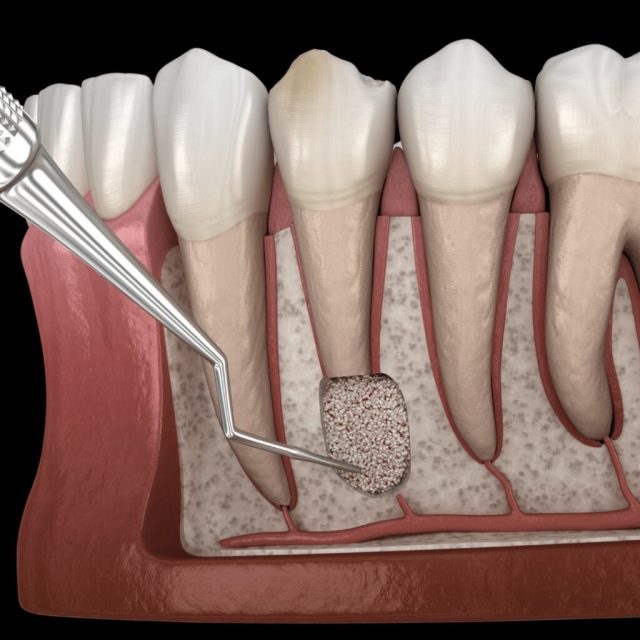

3. Резекція кістки. За допомогою спеціальних інструментів видаляється невелика ділянка кісткової тканини, щоб оголити верхівку кореня.

4. Зріз кореня. Хірург відсікає пошкоджену частину кореня та видаляє запалені тканини (гранульому або кісту).

- ▪ використання додаткових матеріалів, наприклад, замінного матеріалу для відновлення кісткової тканини